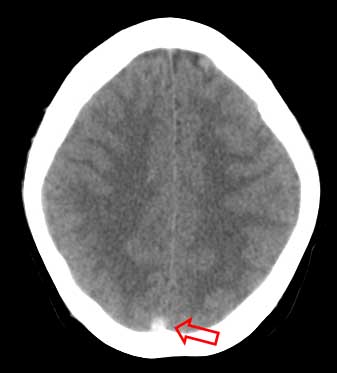

En el mismo paciente, un corte más apical en la TC craneal sin contraste (a la izquierda) muestra la hiperdensidad del seno longitudinal (flecha) por trombosis. La imagen de la derecha es una reconstrucción sagital de línea media del angioTC. La flecha señala un defecto de repleción por trombo en el interior del seno. Existe otro defecto más anterior. Se trataba, pues, de una trombosis parcial. Por esa razón no se ve el signo del triángulo denso en el primer corte.